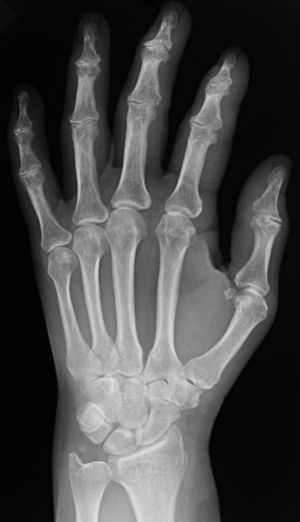

의학 영상에서 사용되는 방사선 촬영술에는 투사 방사선 촬영술과 투시경 검사 두 가지 형태가 있다. 이 두 가지 기술은 3차원 단층 촬영술이 발전했음에도 불구하고 비용이 저렴하고 해상도가 높으며, 적용 분야에 따라 방사선량을 줄일 수 있어 여전히 널리 사용된다. 이 영상 기술은 넓은 X선 빔을 사용하여 영상을 획득하며, 현대 의학에서 사용 가능한 최초의 영상 기술이다.[1]

X선 촬영은 단순 X선 촬영, X선 투시 촬영, X선 단층 촬영으로 나눌 수 있다.

3. 1. 1. 단순 X선 촬영

투사 방사선 사진은 일반적으로 X선 촬영이라고 불리며, 뼈의 골절 유무와 종류, 범위를 파악하거나 폐의 병리학적 변화를 감지하는 데 자주 사용된다. 방사선 불투과성 조영제인 바륨을 사용하면 위와 장의 구조를 시각화하여 궤양이나 특정 유형의 결장암을 진단하는 데에도 도움을 줄 수 있다.[1] X선을 한 방향에서 짧은 시간 동안 조사하여 정지 영상을 얻는 방법이다.[2]